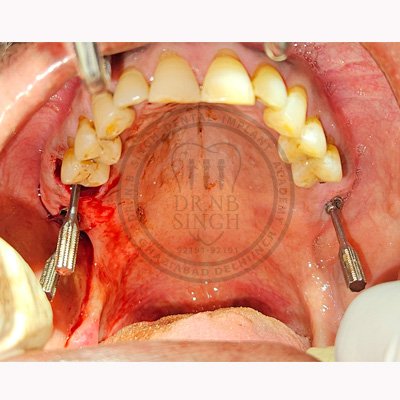

Case – 11 Baleram